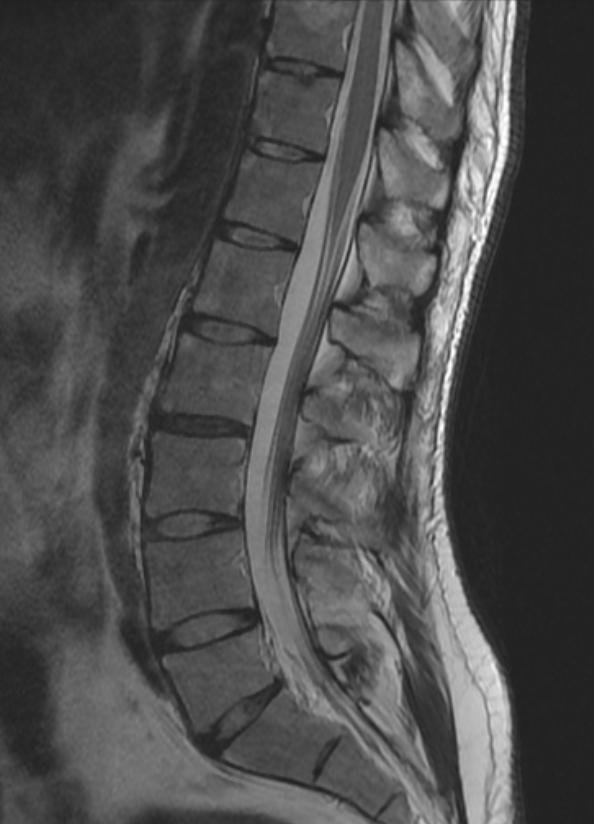

70y/o👩🏾‍🦳.Expansile lession w/mild mass effect on the conus medullaris&cauda equina. Scalloping of the posterior elements. HighT2 signal No DWI anomaly. Most likely spinal(apparently)extradural arachnoid cyst. Same date brain MR:no brain sag nor congestion #spinerad @The_ASSR

josealejandrobv's tweet image. 70y/o👩🏾‍🦳.Expansile lession w/mild mass effect on the conus medullaris&cauda equina. Scalloping of the posterior elements. HighT2 signal No DWI anomaly. Most likely spinal(apparently)extradural arachnoid cyst. Same date brain MR:no brain sag nor congestion #spinerad @The_ASSR